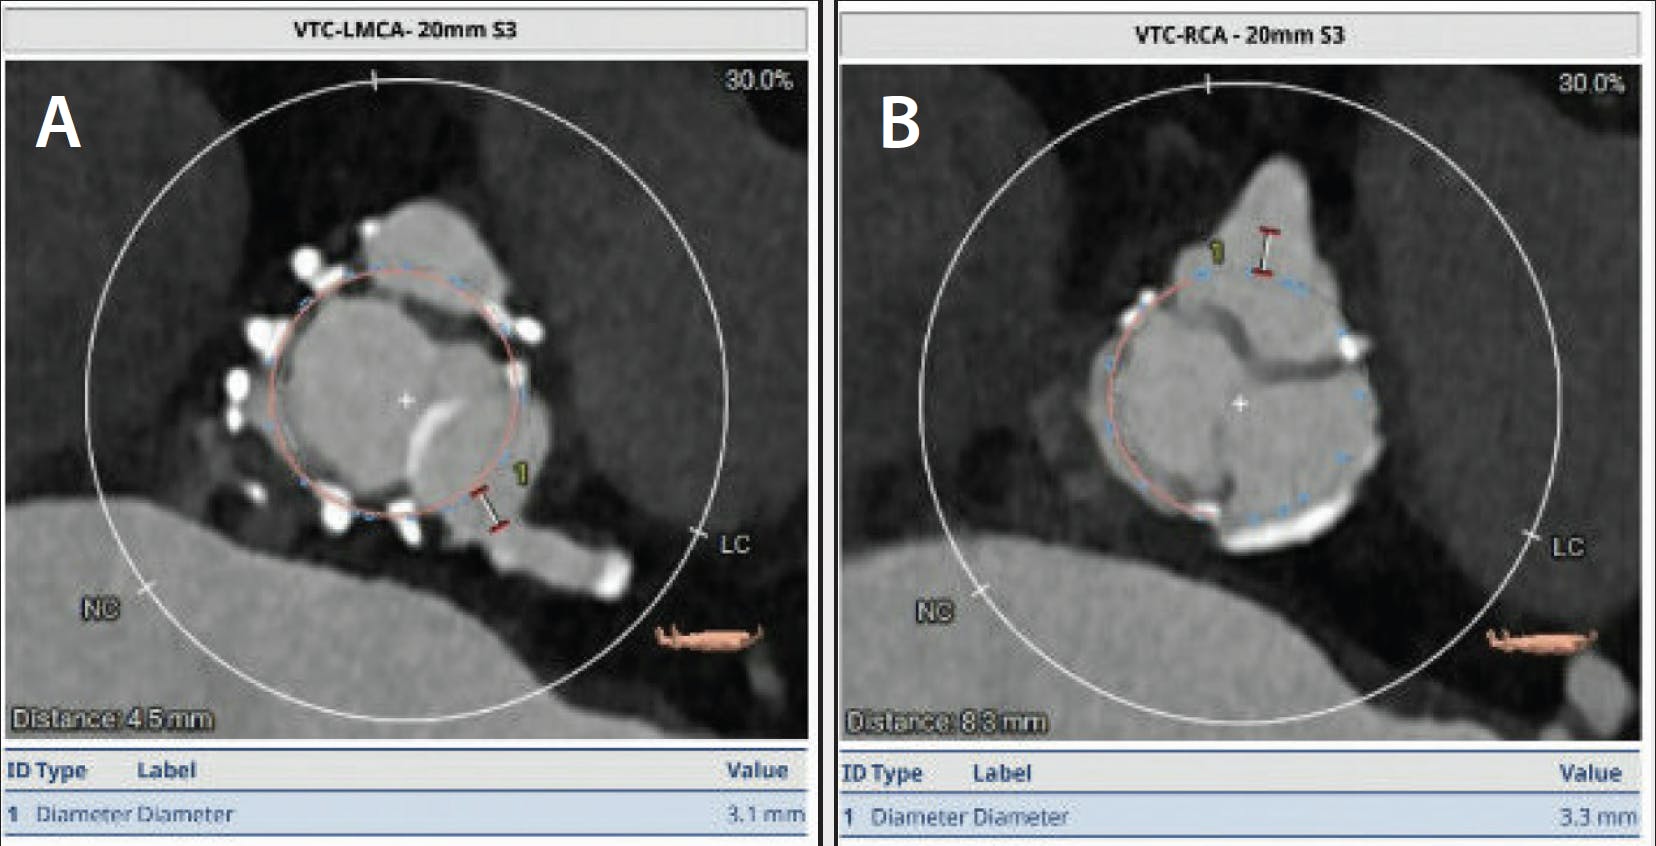

Transthoracic echocardiography demonstrated an aortic valve area of 0.6 cm2, a mean gradient of 43 mm Hg, peak velocity 4.1 m/s, and a dimensionless index of 0.2, consistent with severe prosthetic valve stenosis. Cardiac CT revealed low coronary heights (3.7 mm from the left coronary sinus with THV-VTC distance to the left main of 3.1 mm; 5.8 mm from the right coronary sinus with THV-VTC distance to the right coronary artery of 3.3 mm) (Figure 1 and Figure 2).

Figure 1. CT analysis: coronary heights.

Figure 2. CT analysis: THV-VTC of the left main coronary artery (A) and RCC (B).